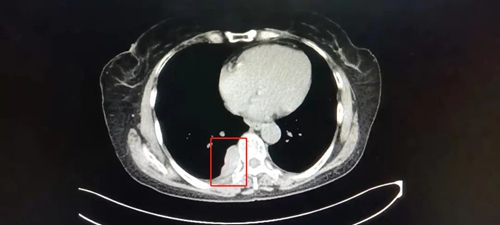

患者陈女士,59岁,因右侧胸背部疼痛半个月来我院就诊,经检查,胸部Ct结果显示:T8椎体旁紧贴胸膜处占位病变,且气管有先天畸形改变。陈女士既往有冠心病、高血压病和甲亢病史,家庭贫困。考虑其家庭状况,经充分术前评估,主管医生葛庆升详细告知陈女士病情及诊疗方案后,陈女士及其家属反复思量要求在家乡医院进行手术治疗。在郑州大学第二附属医院苏彦河教授的技术指导下,胸外科团队制定了周密的诊疗方案,因无法为陈女士完成单肺呼吸麻醉,经麻醉科会诊后,决定对其施行人工气胸胸右侧胸腔镜下纵膈肿瘤切除术,人工制造气胸,在纵膈中自下向上极度精准的操作,切除肿瘤。手术过程十分顺利,术中几乎无出血,术后患者恢复良好,现已康复出院。

![]() ![]() (术后CT) | ||